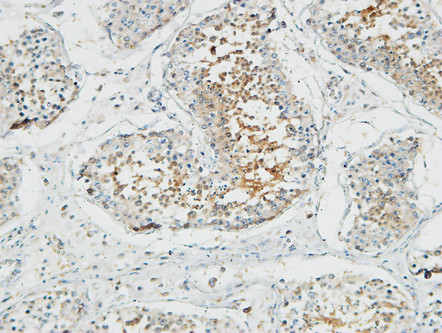

分类: 科研抗体货号: P23172别名: STEAP2; PCANAP1; STAMP1; Metalloreductase STEAP2; Prostate cancer-associated protein 1; Protein up-regulated in metastatic prostate cancer; PUMPCn; Six-transmembrane epithelial antigen of prostate 2; SixTransMembrane protein of prostate 1应用: IHC,IF反应种属: Human,Mouse